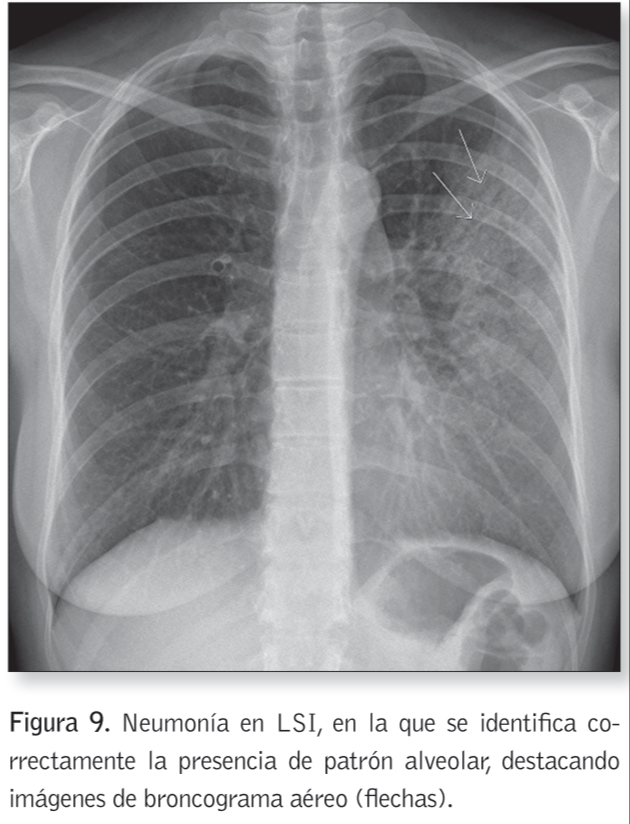

Signo del broncograma aéreo